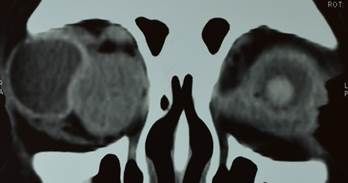

Celulitis Orbitaria

• No es común pero es una condición importante que puede tener complicaciones sistémicas y oculares serias.

• Signos más frecuentes

– Motilidad ocular limitada

– Proptosis

– Quemosis

– Hiperemia conjuntival

– Fiebre y leucocitosis (sugerentes)

– Pérdida de la visión

– DPA

– Falta de distinción de colores

• Un retraso en el tratamiento puede resultar en morbilidad significativa incluyendo:

– Síndrome del apex orbitario (oftalmoplejia externa e interna, ptosis, sensación corneal disminuida y pérdida de la visión)

– Trombosis del seno cavernoso

– Parálisis de N. craneales

– Meningitis

– Formación de abscesos intracraneales

– Muerte

Su atención y tratamiento antibiótico y quirúrgico son de especial importancia para una resolución favorable.